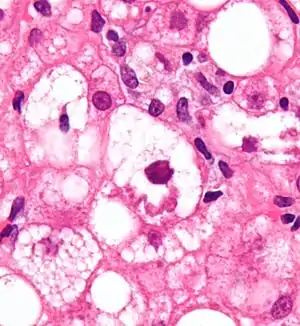

| Micrograph showing a Mallory body, a histopathologic finding associated with alcoholic hepatitis. H&E stain. | |

- Mallory's hyaline body – a condition where pre-keratin filaments accumulate in hepatocytes. This sign is not limited to alcoholic liver disease, but is often characteristic.[6]

- Inflammation – neutrophilic invasion is triggered by the necrotic changes and presence of cellular debris within the lobules. Ordinarily the amount of debris is removed by Kupffer cells, although in the setting of inflammation they become overloaded, allowing other white cells to spill into the parenchyma. These cells are particularly attracted to hepatocytes with Mallory bodies.[6]